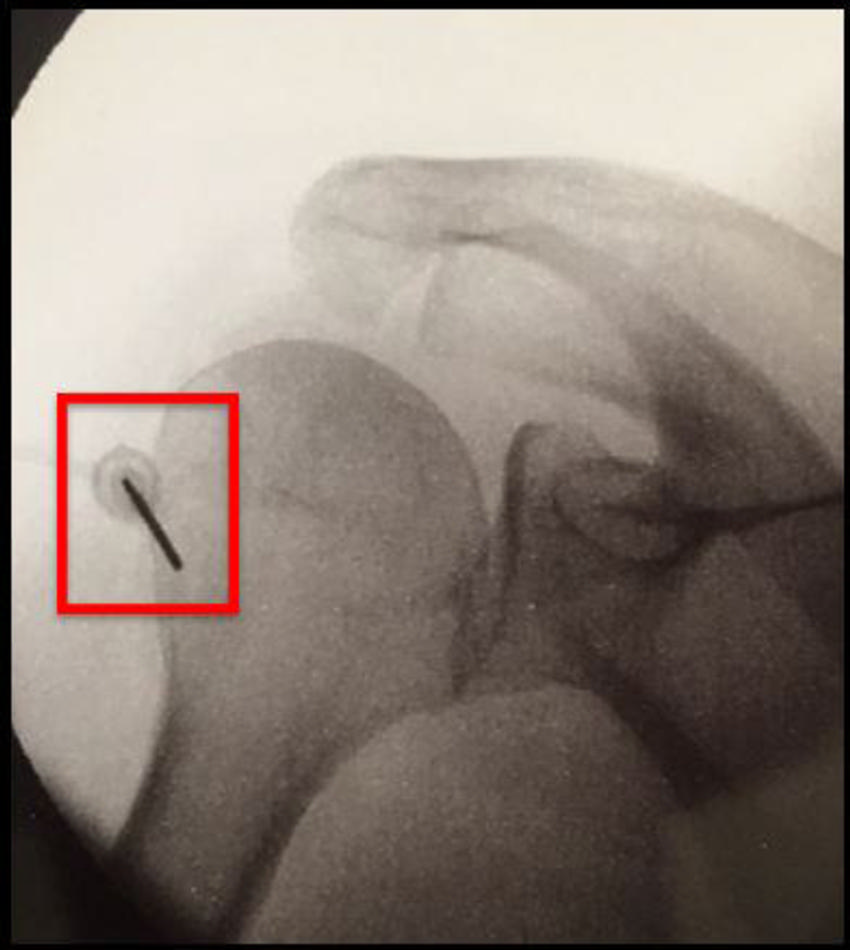

Figure 12. Hip-specific cooled radiofrequency ablation technique: There are three ablation targets.

Figure 13. Hip cooled radiofrequency ablation: Obturator nerve ablation.